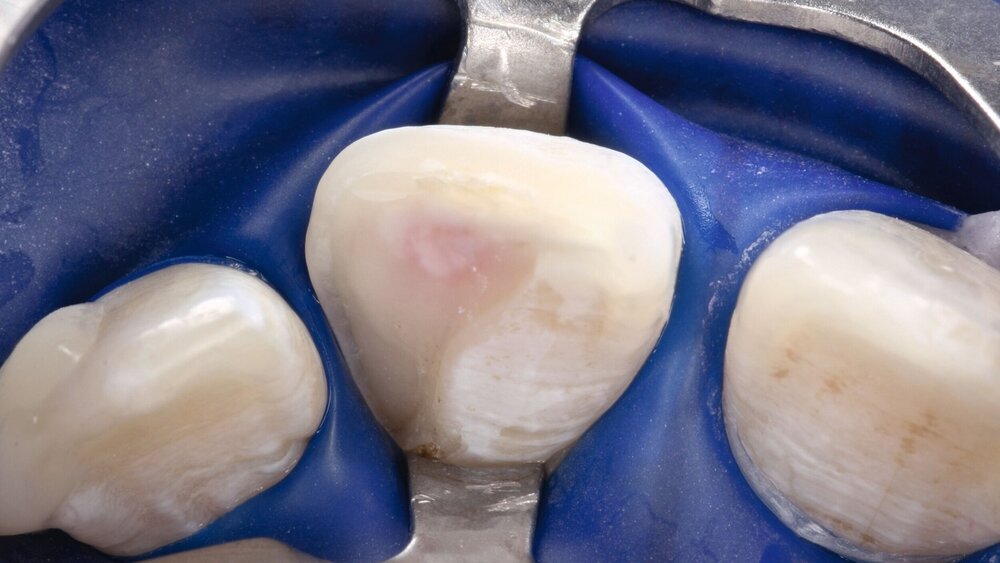

Darüber hinaus muss man bei der Erörterung konventioneller Zementunterfüllungen realistischerweise immer in Betracht ziehen, dass niemals jedes einzelne Dentinkanälchen von Zement bedeckt sein wird und somit selbstverständlich immer zusätzlich mit einem Adhäsivsystem (für Schmelz und Dentin) gearbeitet werden muss. Dies gilt vor allem für die Approximalbereiche, in denen der Abstand zur Pulpa oft geringer ist als okklusal (Abbildung 1).

Eine besondere Situation stellt die Caries profunda dar. Hier gibt es hinreichend Evidenz, dass unterhalb einer Restdentindicke von 300 μm zum einen die Gefahr besteht, dass kurzkettige Monomere das Dentin durchdringen und Biomineralisationsprozesse der Odontoblasten stören können [Galler et al., 2011; Schmalz et al., 2001]. Praktisch viel wichtiger ist jedoch ein rein geometrisches Problem: Bondet man eine Kompositrestauration im Dentin so nahe an der Pulpa, bilden sich neben der für die Dentinhaftung verantwortlichen Hybridschicht auch Harzzotten (Resin Tags), die bis zu 300 μm in das Dentin eindringen (Abbildung 2). Das würde bedeuten, dass sich die Tags praktisch am Eingang der Pulpa befinden, was weder klinisch noch anatomisch sinnvoll erscheint. Gleiches gilt für pulpanahe Bereiche bei Kronenfrakturen. Insbesondere bei Kindern sind die Dentintubuli noch weit offen und das Dentin ist an diesen Stellen hoch permeabel [Krastl et al., 2021].